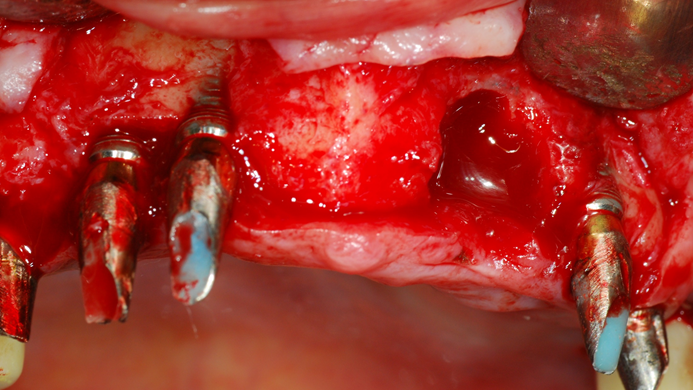

“Achieving a clean surface is the key to treating peri-implantitis!Using a titanium or NiTi brush for the decontamination process along with proper GBR can successfully restore the peri-implant environment. ”

Clinical case: Peri-implantitis treatment case using titanium or NiTi brush

- Courtesy of Dr. Dae-Hee Lee, South Korea -

Dr. Dae-Hee Lee,Maxillary Anterior,Peri-implantitis,Bone regeneration,Aesthetic zone,#21,#22,GBR,Titanium Brush Set